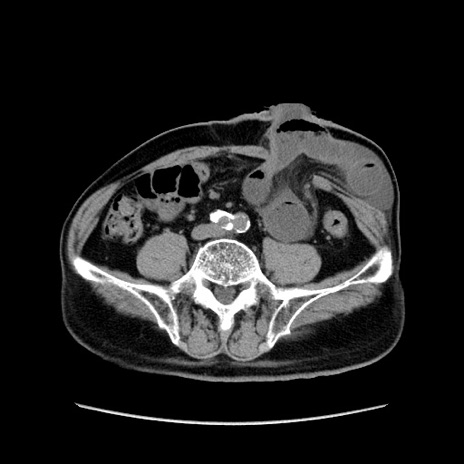

症例24(横断像)

【症例】80歳代男性

【主訴】左側腹部痛、嘔吐

【現病歴】本日早朝より左腹部に痛みあり。昼頃嘔吐認めたため、救急要請。

【既往歴】直腸癌(Mile手術)、胆摘

【身体所見】意識清明、BT 35.9℃、BP 221/93mmHg、SpO2 97%(RA) 、腹部:左ストーマ周囲に限局性の腹部膨隆あり。 膨隆部自発痛・圧痛あり・軟。

【データ】WBC 7700、CRP 0.09